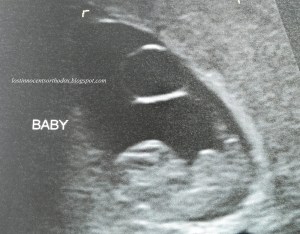

Elexus’s baby, Adam Scott Terry Jr. (measuring 4 weeks, ultrasound done at 4 weeks, 4 days)